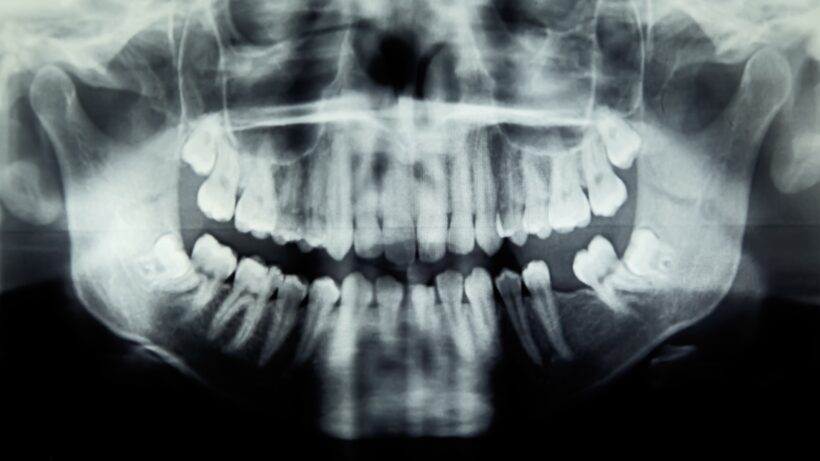

Компьютерная томография выявила сильное воспаление правых пазух носа, смещение жировой ткани вокруг глаза и субпериостальный абсцесс (скопление гноя в глазнице).